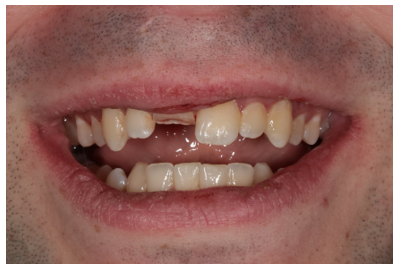

A 22-year-old patient presented to a prosthodontic practice with an complicated fracture of a maxillary central incisor (Fig. 1). The patient was transported to the dental clinic after experiencing trauma to the maxillary anterior teeth during physical fitness training. #8 displayed a mid-crown complete horizontal fracture, the pulpal tissue was exposed, no mobility, and the patient reported a moderate amount of sharp constant pain (Fig. 2). A pulpal and periapical diagnosis of symptomatic irreversible pulpitis and normal apical tissue was made. No other injuries were noted to adjacent teeth or intraoral and extraoral tissue. The fractured segment was brought with the patient and after cleaning with sterile saline it could be easily aligned back on the tooth and the margins displayed a clean fracture (Figs. 3 and 4). The patient was esthetically demanding and required a quick and long-term solution to return back to training as he was a student at Fort Eisenhower. The patient was scheduled for an overseas mission shortly after his school ended.

Figure 4: Re-articulation of fractured segment back on to tooth.